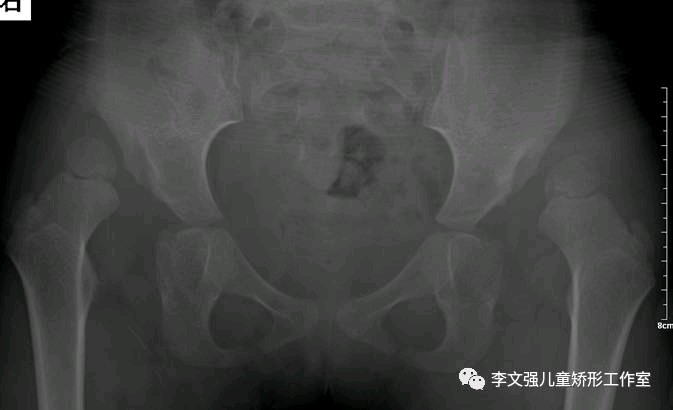

小儿发育性髋关节脱位是一种常见的髋关节疾病,女孩多于男孩。病变累及髋臼、肌骨头、关节囊、韧带和附近的肌肉,导致关节松弛,半脱位或脱位。

不同年龄应采用不同的治疗方法:(1).半岁以内:用Pavlik吊带治疗(2).半岁~1岁半:人类位石膏固定。一般治疗6~9个月。(3).1岁半~2岁:可以人类位石膏治疗或手术治疗。(4).2岁以上:需要手术治疗。分别是Salter手术、Pemberton手术和Chiari手术。

双侧DDH,行双侧Salter截骨矫形+股骨近端短缩去旋转截骨手术